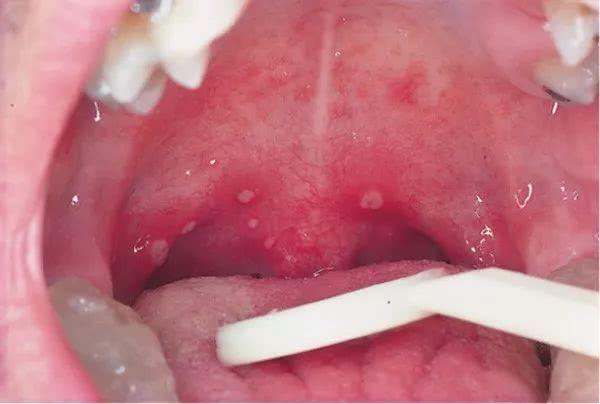

具体体征:咽部充血,在咽腭弓、软腭、悬雍垂的周围黏膜上可见数个或数十个2-4mm大小灰白色疱疹,周围有红晕,1-2日后破溃形成小溃疡,表面附有浅黄色或白色假膜。